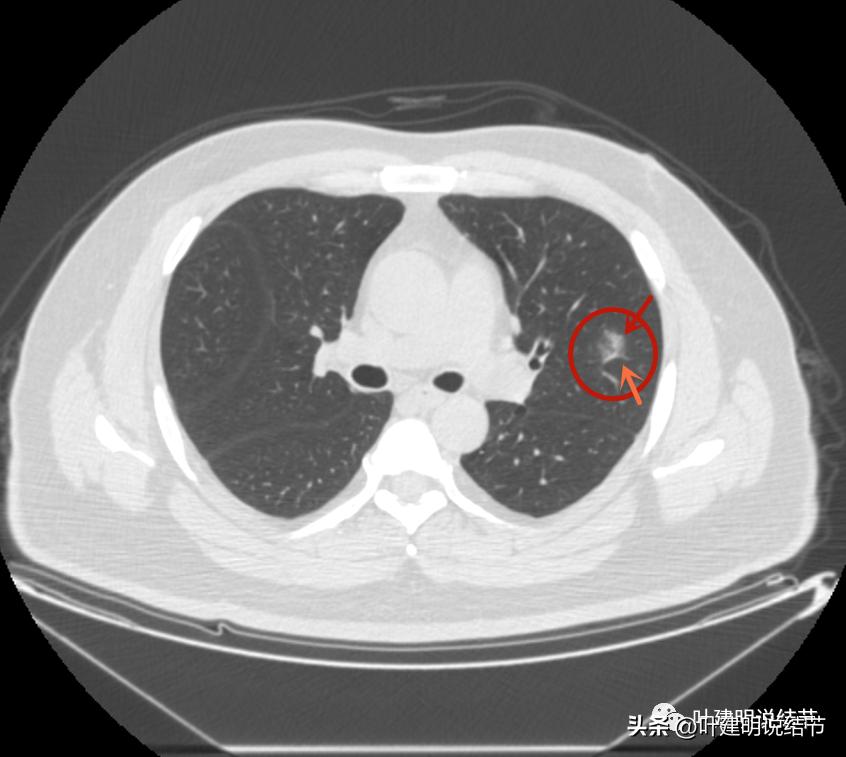

后续再看2022年8月的CT图像,有点惊掉下巴的感觉:

左上叶的病灶1、2、3都没有了!!!完全没有了!那当然说明是炎症性的,居然全部吸收了!

但左上病灶4仍在,形态也没有明显变化,无好转,也无明显进展。这是肿瘤性质的吗?虽然存在2年多了,但因为它的兄弟们都不见了,让我对它认定的肿瘤范畴也产生了怀疑,也许是纤维增生而已呢!